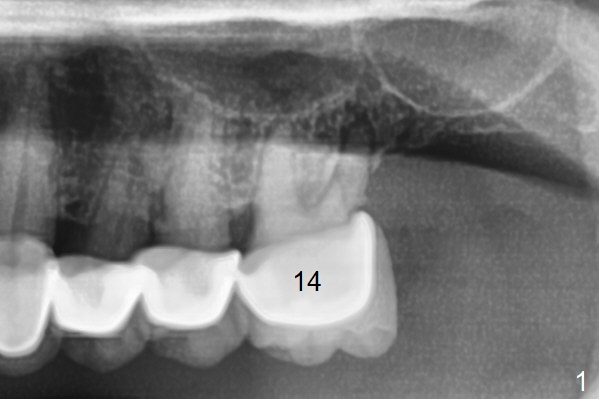

Septum Lower Than Crests

A 53-year-old man requests extraction of the tooth #14 (Fig.1) with pathology mainly around the distobuccal root. It appears that the septum (Fig.2 S) is lower than the crests (C), particularly distally, which is consistent clinically. After placement of Vanilla bone in the thin sockets (relatively large septum, Fig.3), collagen plug and sutures keep the bone graft in place (Fig.4).